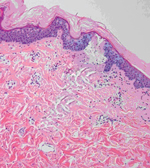

Рис.1. Схематичне зображення зон фотокоагуляции (МТЗ) і фотобіомодуляціі після впливу лазерного променя на гістологічному зрізі шкіри людини (Джастін Мунхен З, MD, медичний директор компанії Dinona inc., Південна Корея) Забарвлення - ГЕ, х100

Основним хромофором для лазерного випромінювання з довжиною хвилі 1550 нм, що генерується лазерною системою Sellas, є що міститься в шкірі вода, тому нагрів, а отже і коагуляція тканини, відбувається в нижніх шарах епідермісу і в дермі. При впливі лазером Sellas верхні шари епідермісу, що містять мінімальну кількість води, практично не пошкоджуються. У процесі впливу лазерний промінь створює в шкірі мікротермальние зони (МTЗ) - зони фотокоагуляции в формі стовпчиків, перпендикулярних поверхні шкіри, шириною до 220 мкм, глибиною до 1500 мкм, оточені областю фотобіомодуляціі, яка володіє підвищеним потенціалом відновлення (рис.1) 2, 3.

Зони фотокоагуляции вирішуються асептическим запаленням, в процесі якого частина некротичних уламків фагоцитируется мігруючими в цю зону макрофагами, а що залишилися виходять на поверхню шкіри. Протягом 24-48 годин після впливу базальний шар епідермісу повністю відновлюється. Евакуйовані некротичні уламки отшелушиваются протягом 4-14 днів (Рис. 2). Вважається, що швидкість відновлення базального шару залежить від діаметра первинного мікроповрежденія4-6.